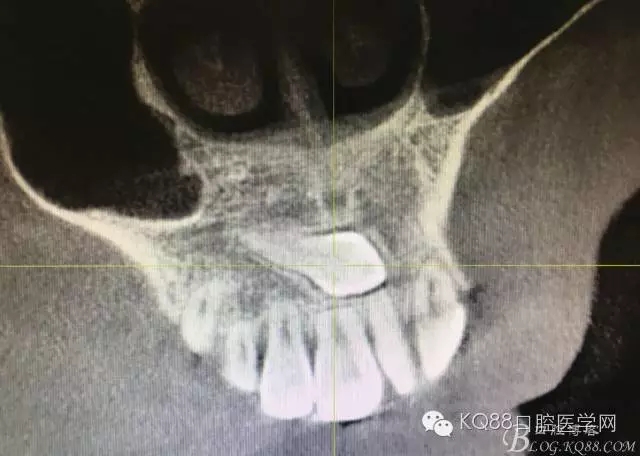

圖4. 冠狀面檢查情況 :